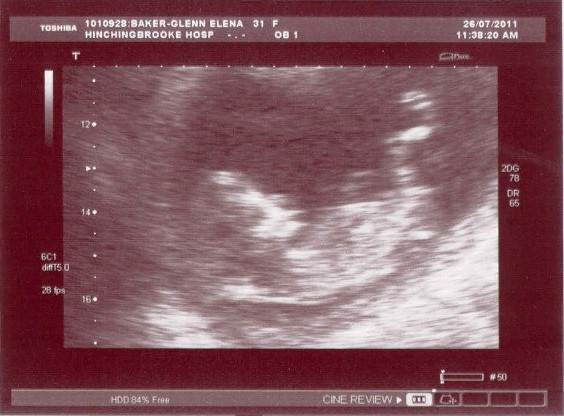

These are the photos of the 12 week scan taken on 26/7/11 at 12+2 weeks gestation. The due date is 5th February.